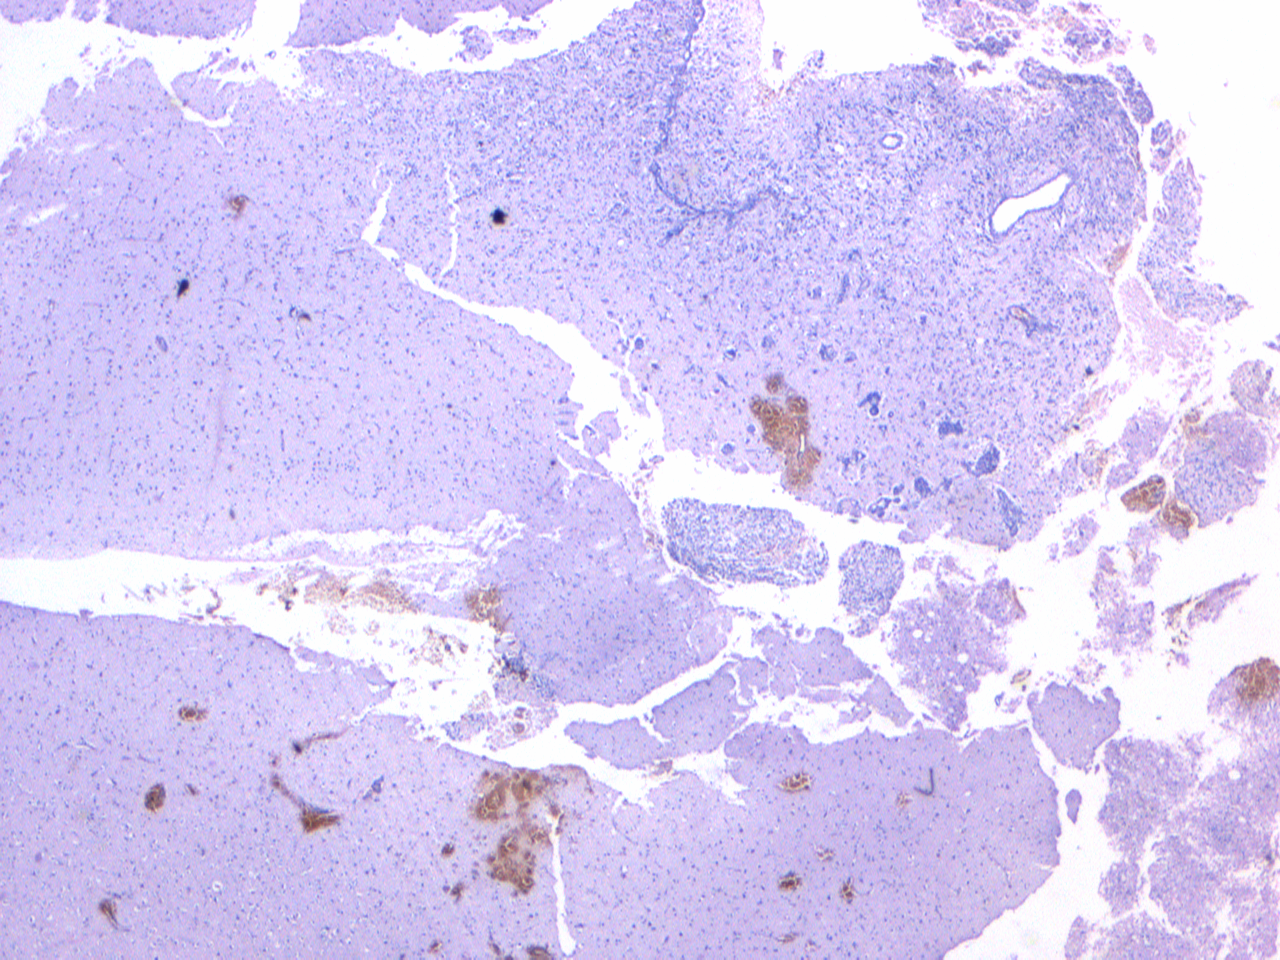

Oligodendroglioma

An oligodendroglioma, with the chicken ('wire') and the egg ('fried')